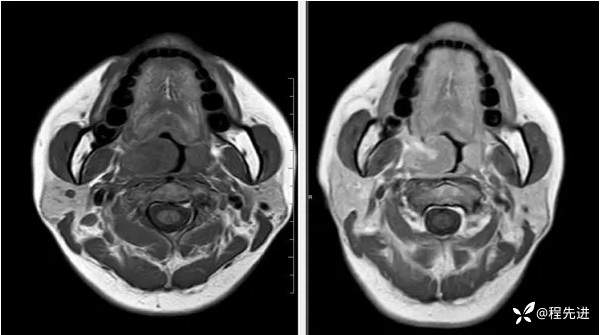

T1及T1增强: